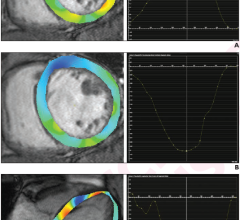

Royal Philips recently received 510(k) clearance from the US Food and Drug Administration (FDA) for its detector-based ...